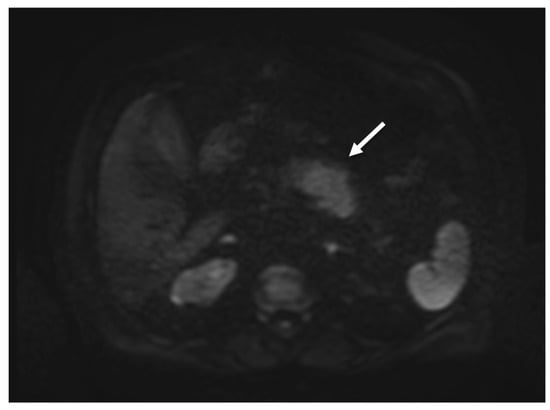

2. Case Report